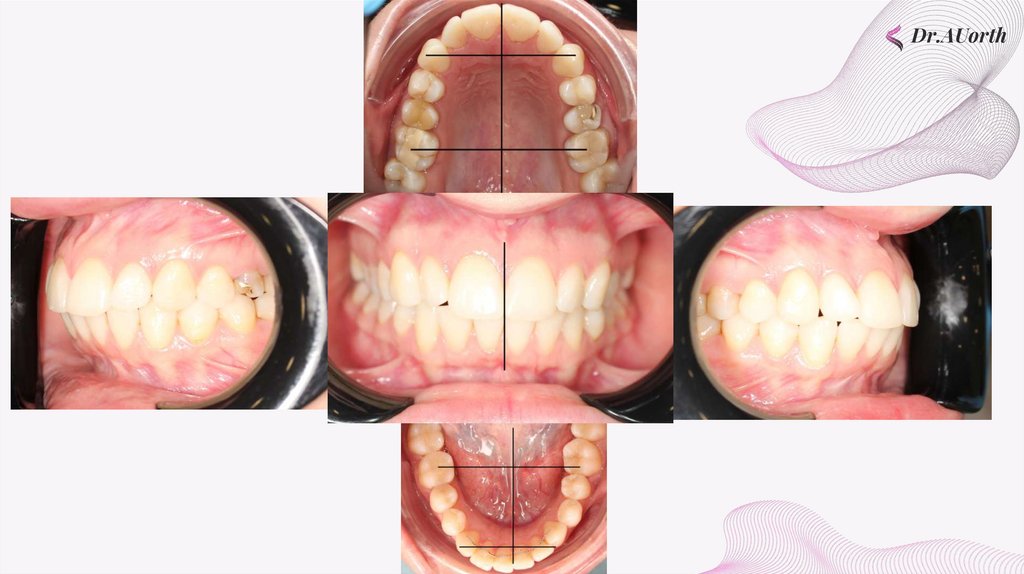

внутриротовые фотографии

Первый класс по клыкам справа, первый - по клыкам слева.

Сагиттальная щель отсутсвует. Протрузия резцов на нижней, верхней

челюсти отсутствует. Обратное перекрытие зуба 2.4

Окклюзионные фотографии

Сужение периметра верхней, нижней челюсти. Соотношение по

Герлаху не совпадает